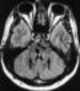

Tumor at fourth ventricle

An ependymoma is a tumor that arises from the ependyma, a tissue of the central nervous system. Usually, in pediatric cases the location is intracranial, while in adults it is spinal. [Source: Wikipedia ]